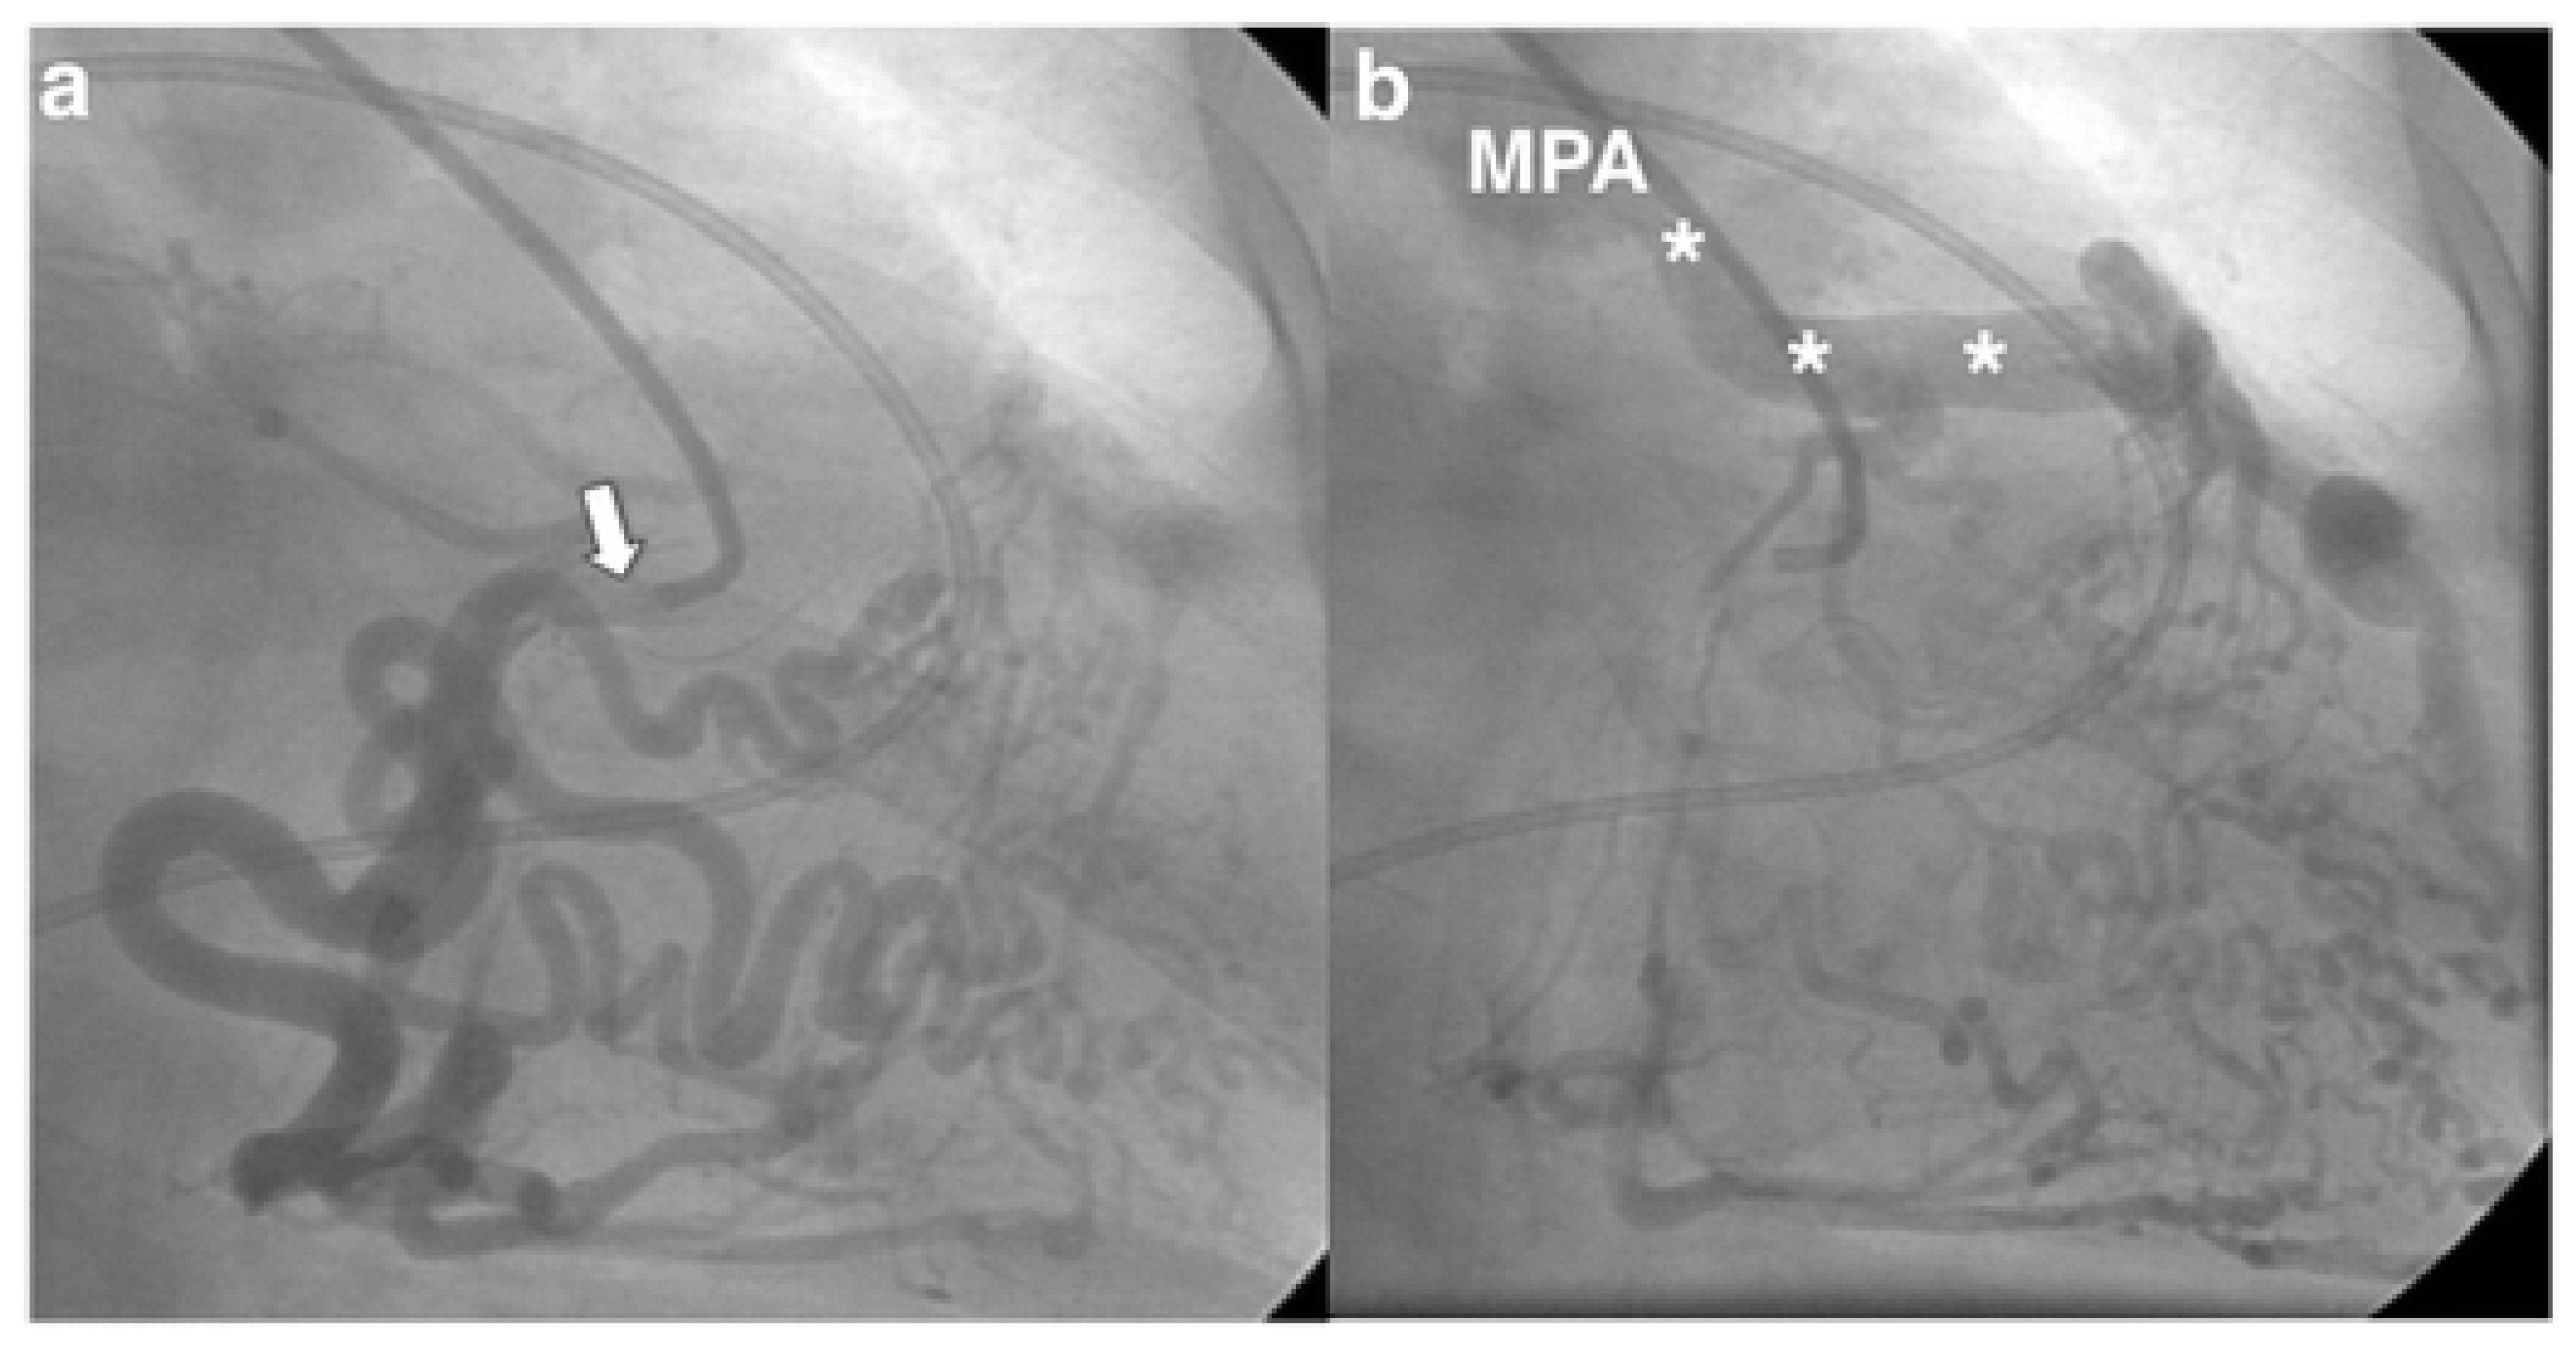

Invasive coronary angiography (ICA) was the standard for ALCAPA diagnosis as it depicted the course of the anomalous coronary artery; however, it has been largely replaced by noninvasive diagnostic testing. However, during the course of a workup for angina, the patient may undergo ICA and be found to have ALCAPA incidentally. Typical findings on ICA include a dilated and tortuous right coronary artery with multiple collaterals to the left coronary system; anomalous flow into the pulmonary artery can also be seen (Figure 1) [7]. Transthoracic echocardiogram (TTE) with color Doppler is a safe, readily available, inexpensive, and portable noninvasive method for initial investigation used in all patients (Table 1). Echocardiographic findings indicative of ALCAPA include visualization of the left coronary artery originating from the pulmonary artery (Figure 2), retrograde flow from the left coronary artery to the pulmonary artery (Figure 3), dilated and tortuous right coronary artery, lack of the left coronary artery at aortic origin, significant and dilated collateral coronary arteries, mitral regurgitation, left ventricular dysfunction with regional wall motion abnormalities, and enhanced echogenicity of papillary muscles [9,10,11]. The parasternal short-axis acoustic window on TTE provides the best views of the origins of the coronary arteries. Increased flow in the minor coronary arteries due to the collateral flow from the right to the left coronary artery may be detected by lowering the Nyquist limit. In younger patients with dilated right coronary artery, collateral arterial flow in the ventricular septum may be seen and misdiagnosed as multiple trabecular ventricular septal defects. In order to distinguish between these two, pulse-wave Doppler should be performed: continuous flow in the collateral vessels is noted in patients with ALCAPA, while systolic flow into the right ventricle is noted in patients with ventricular septal defects [11]. Transthoracic echocardiogram, while fast and easy, has poor spatial resolution, making it difficult to identify and visualize the arteries; thus, it should be supplemented with further diagnostic testing such as computed tomography angiography (CTA), magnetic resonance angiography (MRA), or ICA [4].

Figure 1. (a) Selective angiography of the right coronary artery (white arrow) revealing a dilated and tortuous vessel with multiple collaterals to the left coronary artery. (b) The injected intrave-nous contrast spills from the left coronary artery into the main pulmonary artery (MPA; asterisks), confirming anomalous left coronary artery from the pulmonary artery. Used with permission from Crean, A.; Ahmed, F.; Motwani, M. The Role of Radionuclide Imaging in Congenital Heart Disease. Curr. Cardiovasc. Imaging Rep. 2017, 10, 38. https://doi.org/10.1007/s12410-017-9434-0; Executive Summary. J. Am. Coll. Cardiol. 2019, 73, 1494–1563. [12].